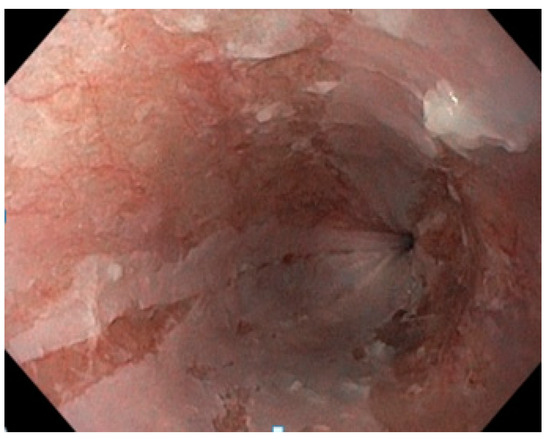

Discussing the case with the patient’s cardiologist, apixaban was discontinued and a treatment with low-molecular-weight heparin twice daily was initiated during her hospital stay. After discharge, a treatment with rivaroxaban was prescribed. She also underwent acid suppression with 40 mg of a PPI (pantoprazole) twice daily and a treatment with an oral iron supplement for six months. A liquid diet was initiated for 24 h. Additionally, she was advised to ingest these medicines with enough water and stay seated for at least 30 min after taking any drugs to prevent them from adhering to the esophageal mucosa. A follow-up upper GI endoscopy at one month revealed a significantly improved esophageal appearance (Figure 2).

Figure 2.

Improved endoscopic appearance of the esophageal mucosa one month after treatment.